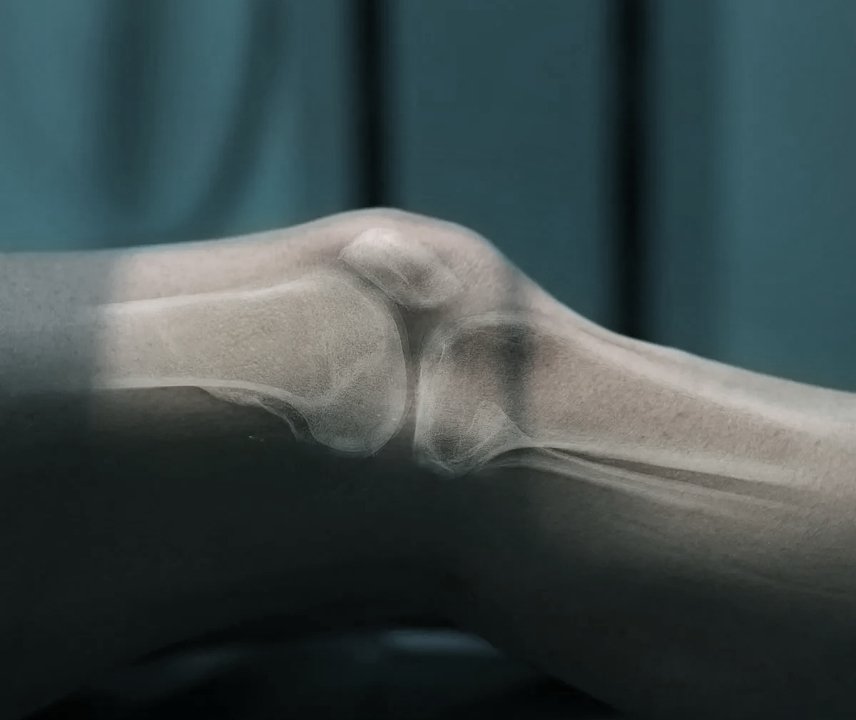

Das Kniegelenk ist ein komplexes Gelenk, das aus verschiedenen Strukturen besteht und eine wichtige Rolle in der Bewegung und Stabilität des unteren Beins spielt. Die Behandlung von Knieverletzungen und Verschleiß kann von konservativen Ansätzen wie Physiotherapie und Medikamenten bis hin zu chirurgischen Eingriffen wie Arthroskopie, Umstellungsosteotomie oder Knieprothesen reichen. Die Wahl der Behandlung hängt von der Art und Schwere der Knieprobleme sowie den individuellen Bedürfnissen und Zielen des Patienten ab. Eine genaue Diagnose und Beratung durch einen Orthopäden ist entscheidend, um die bestmögliche Behandlungsstrategie festzulegen.

Bei Patient:innen mit Trochleadysplasie ist die Gleitrinne der Kniescheibe zu flach ausgebildet, wodurch es zu Instabilitäten und Luxationen kommt. Die Trochleaplastik stellt die natürliche Anatomie wieder her, indem das Gleitlager chirurgisch vertieft und stabilisiert wird. Dazu wird der Knorpel vorsichtig angehoben, das Knochenbett geformt und die Knorpelschuppe mit speziellen Ankern und Fäden fixiert. So entsteht eine funktionelle Laufrinne, die die Kniescheibe stabil führt.